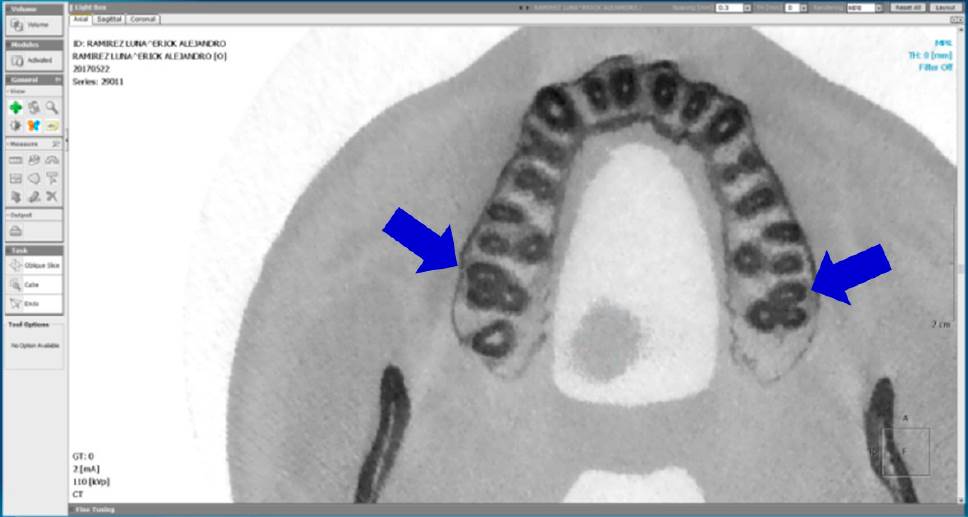

Se realizó el análisis de CBCT a cada diente para confirmar la presencia o ausencia del conducto MV2. Se usó la misma computadora con lector de CD y el programa OnDemand3DTM (Cybermed Inc., Daejeon, Korea). Se consideró presente el conducto, cuando al analizar la imagen tomográfica de la raíz mesial en un corte axial de 0.3mm, desde el piso de la cámara pulpar hasta el ápice, se observara un punto adjunto al conducto MV1, con una trayectoria continua a partir del piso pulpar del conducto hasta el tercio medio como mínimo, en la vista axial (Figura 1-3).

Figura 3 Corte tomográfico desde una vista axial, las flechas señalan un segundo molar maxilar izquierdo y uno derecho con presencia de conducto MV2 en la raíz mesiovestibular.